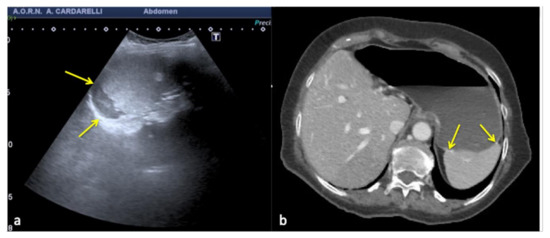

Figure 16. Coronal US scan of the left hypochondrium (a) shows a crescent-shaped hypoechoic area misinterpreted as hematoma (arrows) between the surface of the spleen and the left hemidiaphragm in a 25−year-old man investigated for trauma. On CT scan (b) it appears to be a hypertrophy of the left hepatic lobe with splenic kissing (circle).

Figure 17. Transverse US image of the left hypochondrium (a) shows a large hypoechoic area misinterpreted as splenic hematoma (arrows) in a 31-year-old woman investigated for trauma. On CT scan (b) it appears to be a gastric fundus distended by fluid (arrows).